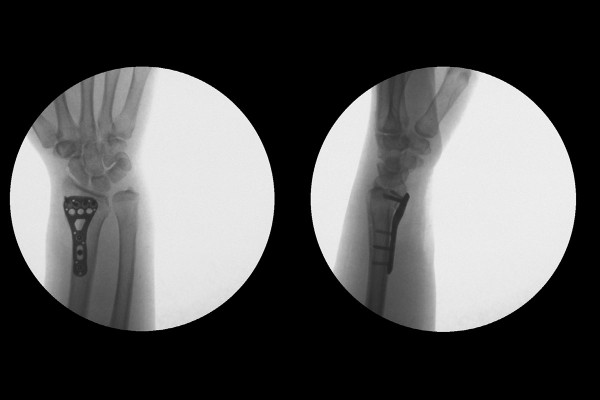

수술 후 X-RAY를 보면 뒤로 꺾인 것 없이 손목이 원래 위치에 맞게 잘 고정되어 있는 것이 확인됩니다.

환자분께서는 현재 3달이 지난 시점에서 내원해주셨고, X-RAY를 보면 금속판이 견고하게 잘 고정해주고 있음을 확인할 수 있습니다.(아무런 문제 없이 직장 생활을 잘 하고 계시다고 합니다.)